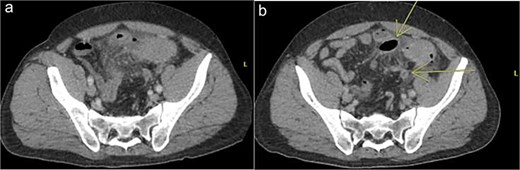

A 44 year old male presented to the hospital with left lower quadrant abdominal pain and diarrhea. Initial workup showed sigmoid diverticulitis with a small pericolic abscess (<3 cm) (Fig. 3a). The patient was admitted to the hospital and treated with bowel rest and IV antibiotics. Unfortunately, the patient failed nonoperative management and repeat CT imaging showed increased extraluminal air (Fig. 3b). He was taken to the operating room on hospital Day 8. Intra-operatively, the patient was found to have purulent peritonitis, left colon diverticulitis, and associated pericolic abscess. He underwent a left colectomy with primary anastomosis. Fluid cultures were obtained. The fascia was closed with #1 non looped PDS and interrupted figure of eight stitches. The umbilicus was approximated with sutures, and a negative pressure subcutaneous wound vac was placed to the midline laparotomy incision and kept on continuous suction at -125 mm Hg. The first wound vac change occurred on POD 2 (Fig. 4a) and then the wound was changed every other day similar to Patient A. DPC was performed on POD 8 (Fig. 4b). The patient’s hospital course was complicated by a prolonged postoperative ileus requiring TPN and an upper GI bleed that was treated medically with PPI therapy. The patient did also have a postoperative abscess that was treated with an IR-guided drain and prolonged antibiotic therapy until POD 20. The patient’s stay was further prolonged due to his initial need for a nursing facility at discharge- he was from out of state and his insurance was not accepted at any facilities. He was ultimately discharged to home on POD 20. The patient was then seen in the office 15 days after discharge and 27 days after DPC on POD 35. The midline incision was healing well and was without any signs of SSI (Fig. 4c).

Patient B. a. Initial CT abdomen and pelvis showing acute diverticulitis with small adjacent abscess. b. Repeat CT abdomen and pelvis with worsening complicated diverticulitis.